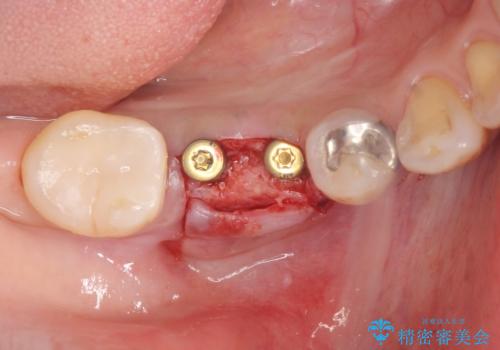

欠損部に1本だけインプラントを埋入しても大きな被せ物になってしまい清掃性が悪くなるので清掃性が良くなるように2本小臼歯用のインプラントを埋入しました。

- 抜歯、歯槽堤保存術・11万円 インプラント体、アバット、仮歯、ジルコニアクラウン・42.9万円×2 骨造成・5.5万円 e-maxインレー・7.7万円 費用は治療当時の料金となります